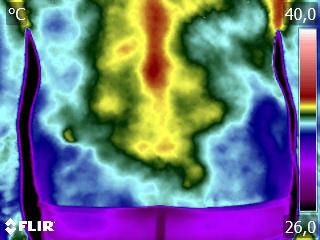

Como no caso do termograma abaixo de um paciente, do sexo masculino, 51 anos, sem comorbidade e que apresentou dor em região lombar. Foi realizado uma Análise Termofuncional e detectado alterações térmicas que corroboraram o relato de dor.

Estas informações permitiram a imediata decisão para a mudança do tratamento e direcionamento da terapia para a diminuição da dor.

Tudo isto em apenas uma sessão.